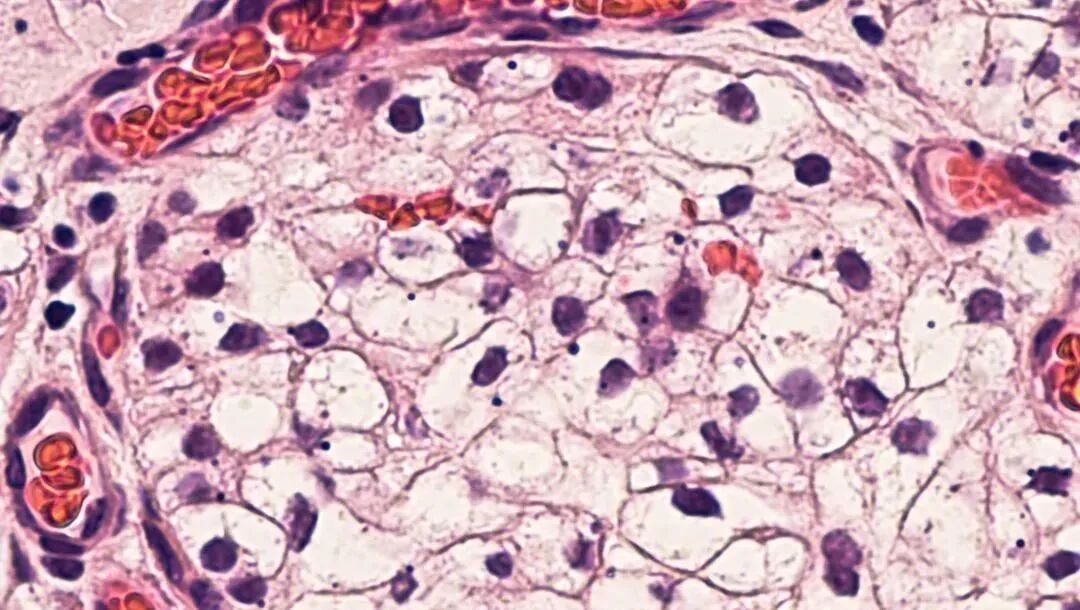

一例62岁的印尼籍妇女,被诊断为胸部截瘫、慢性肾功能衰竭、糖尿病,长期肾脏受累,慢性肾功能衰竭2年,肌酐水平为11 mg/dL,无小便。采用脐带间充质干细胞方案治疗。鞘内注射1.6×107个间充质干细胞,静脉注射1.6×107个间充质干细胞。

临床结果:鞘内注射和静脉注射完三周后,患者可移动脚趾,肾功能得到明显改善,肌酐水平降至9mg/dL。8个月后,患者可以拾起腿,肌酐水平为2mg/dL,小便恢复正常。